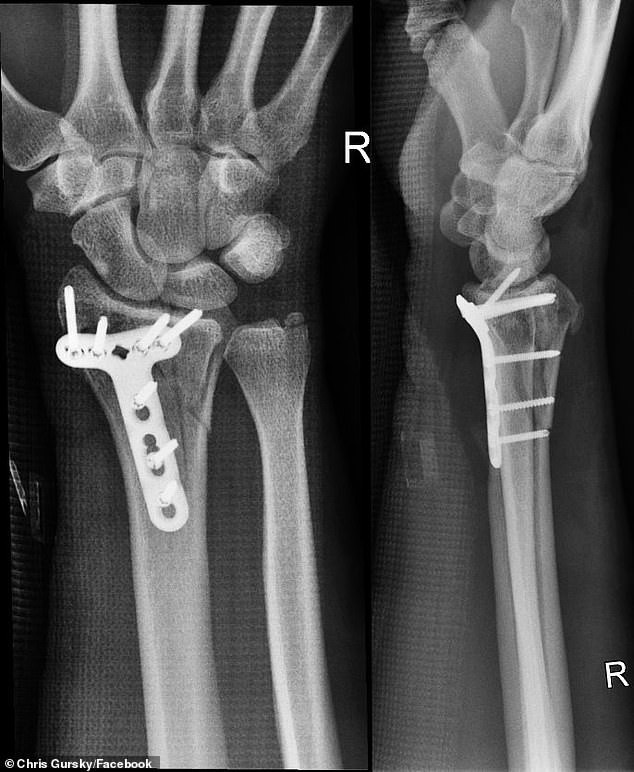

Hoàn cảnh hú hồn này được những chiếc GoPro gắn trên dù lượn ghi lại hết. Sau khi tiếp đất, Chris bị rách cơ tay trái, phải phẫu thuật cổ tay phải vì phải bám víu quá lâu.

2 tay Chris sau khi phẫu thuật